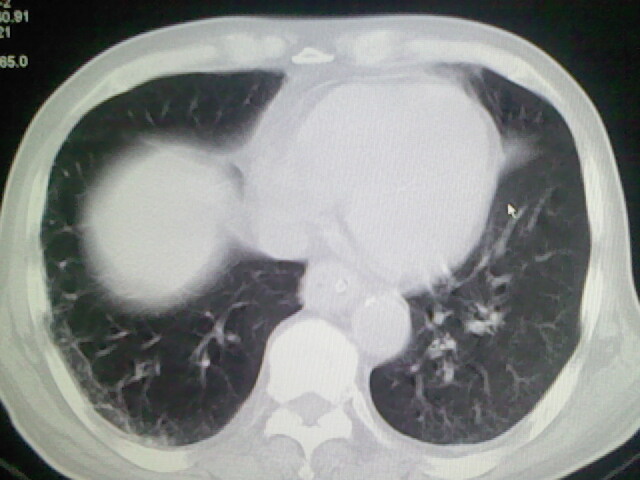

男,70岁,脑出血,长期卧床,左侧背部可触及肿块

右肺病灶考虑炎症性。

右肺病灶考虑炎症性

考虑右肺及左肺下叶炎症。

右肺及左肺下叶炎症。

考虑右肺及左肺下叶慢性炎症。

右侧肺部见片状密度增高影,边缘模糊。考虑炎症。另食管壁增厚。

右肺肺气肿并炎症。

肺气肿并炎症。

右肺上叶前段病呈楔形,其尖端指向肺门,考虑肺动脉栓塞可能性大.